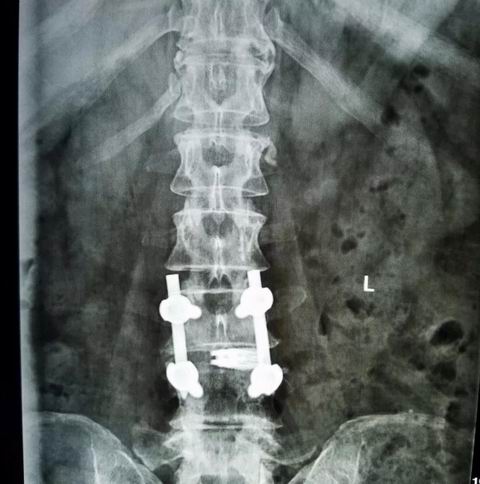

安钢总医院脊柱微创团队在通过仔细分析病人的临床资料与影像学特点后,并在患者拒绝开放手术的要求下,决定采用微创脊柱内镜下融合术preint-ELIF(Endoscopy Lumbar interbody fusion)。脊柱微创团队进行了精心地术前准备,于7月31日上午10点开始手术。手术中,王院长准确定位置管,经椎间孔镜下腰3/4椎间盘减压彻底,扩大手术通道至2厘米,通道下应用终板处理器处理终板,放置大小合适的融合器,最后结合经皮椎弓根螺钉复位脱位的腰4椎体并固定。此微创术式创伤小,术后恢复快,但手术难度大。

在经过整个脊柱微创团队3个小时的奋战后,手术圆满完成,出血量仅为传统手术的六分之一。目前,腰椎融合手术是治疗腰椎间盘疾患的主要方式,应用较多的仍是后路融合术(PLIF),这种手术虽然疗效确切、融合率较高,但需要在后背切开长约10cm的刀口,因为是直接减压,要破坏腰椎的肌肉、小关节、椎板等后柱结构,对脊柱后柱结构破坏较大,另外椎管内瘢痕增生易导致神经受压,故远期效果往往欠佳。微创脊柱内镜下融合术preint-ELIF(Endoscopy Lumbar interbody fusion),从侧路行椎间融合,不但植骨面积大,融合率高,还保留了后柱结构,避免了对椎管内结构的干扰。较传统ALIF及XLIF风险小,preint-ELIF技术简化了手术的过程,减少术中出血与组织创伤,减少术后疼痛与炎性反应导致的粘连,同时缩短住院时间并更有利于患者康复,是一项具有良好发展前景的技术,但此项技术难度较高并需要较长的学习曲线。